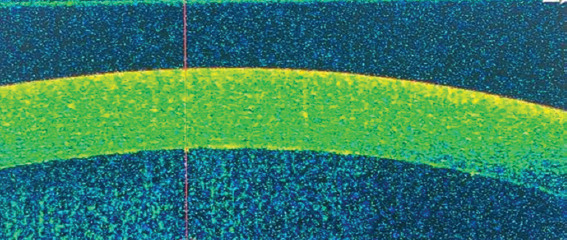

Methods: This longitudinal observational study involved 30 patients diagnosed with or suspected of having rheumatic autoimmune disease presenting with anterior uveitis. The study was conducted at the combined Rheumatology and Ophthalmology Clinic, San Marco Hospital, Catania, Italy. All patients underwent slit-lamp examination, which revealed or suspected corneal endothelial exudates. A comprehensive rheumatological and ophthalmological evaluation was also performed. Subsequently, the patients were subjected to AS-OCT using the Optovue Solix device.

Results: Granulomatous corneal exudates were identified in 30% of the subjects, with counts ranging from 5 to 20 and sizes varying between 50 and 150 μm. Detailed 3D scans further exhibited the morphology of these exudates. A follow-up of patients after steroid therapy (both topical and systemic) and immunosuppressive treatment demonstrated a progressive reduction in the exudates, ultimately leading to their complete resolution.